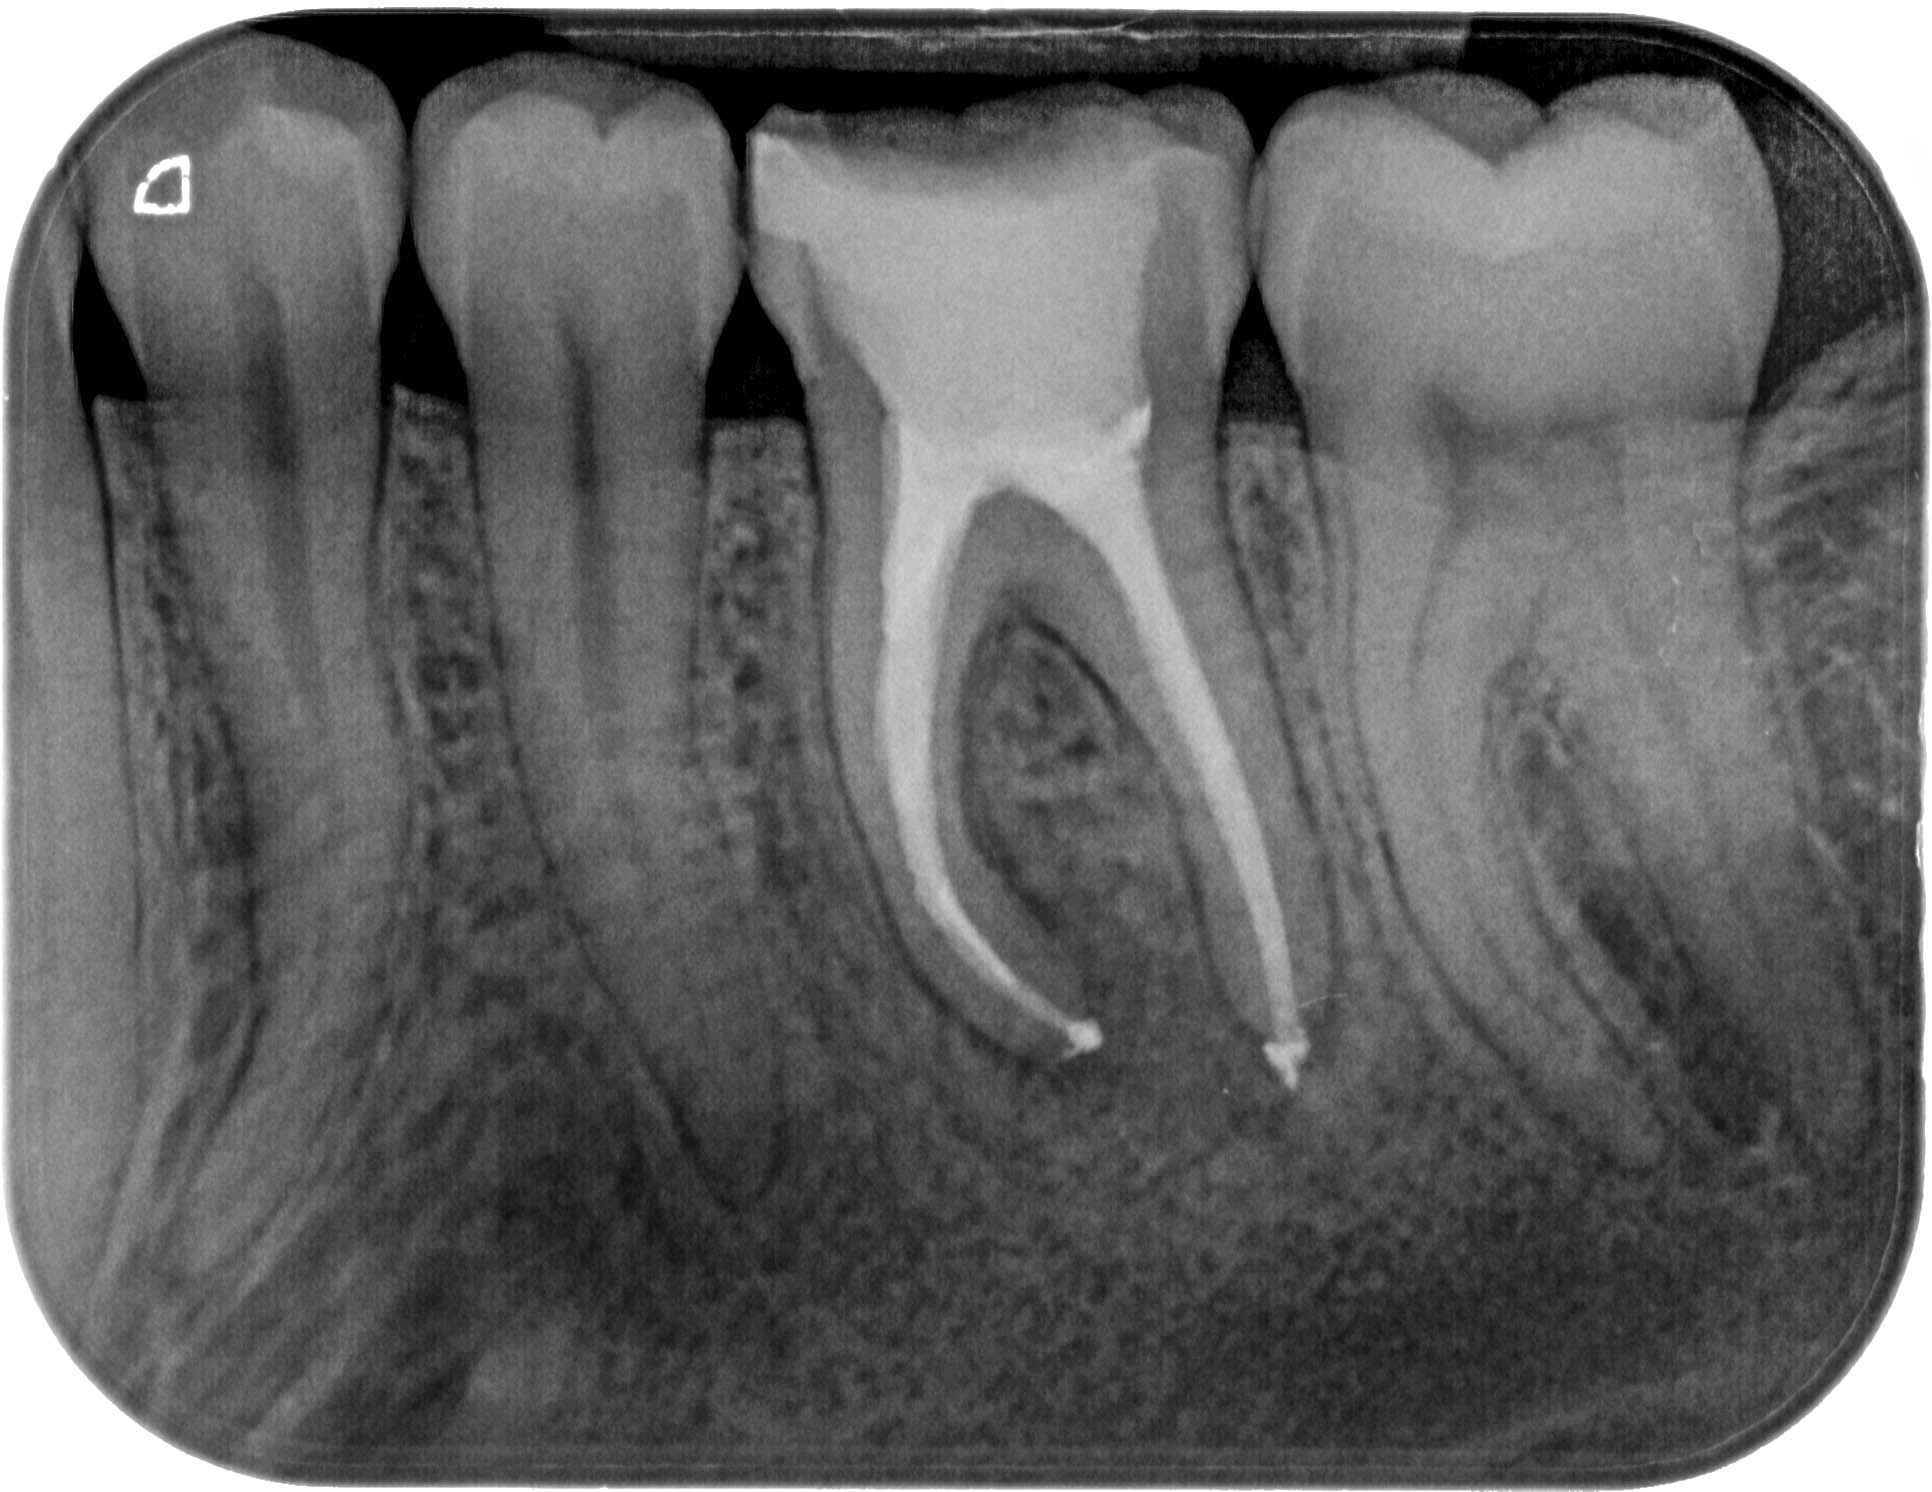

12.06.2012 Veröffentlicht 14. März 2016 am 1932 × 1492 in Calciumhydroxid – Überpressung (1) 12.06.2012